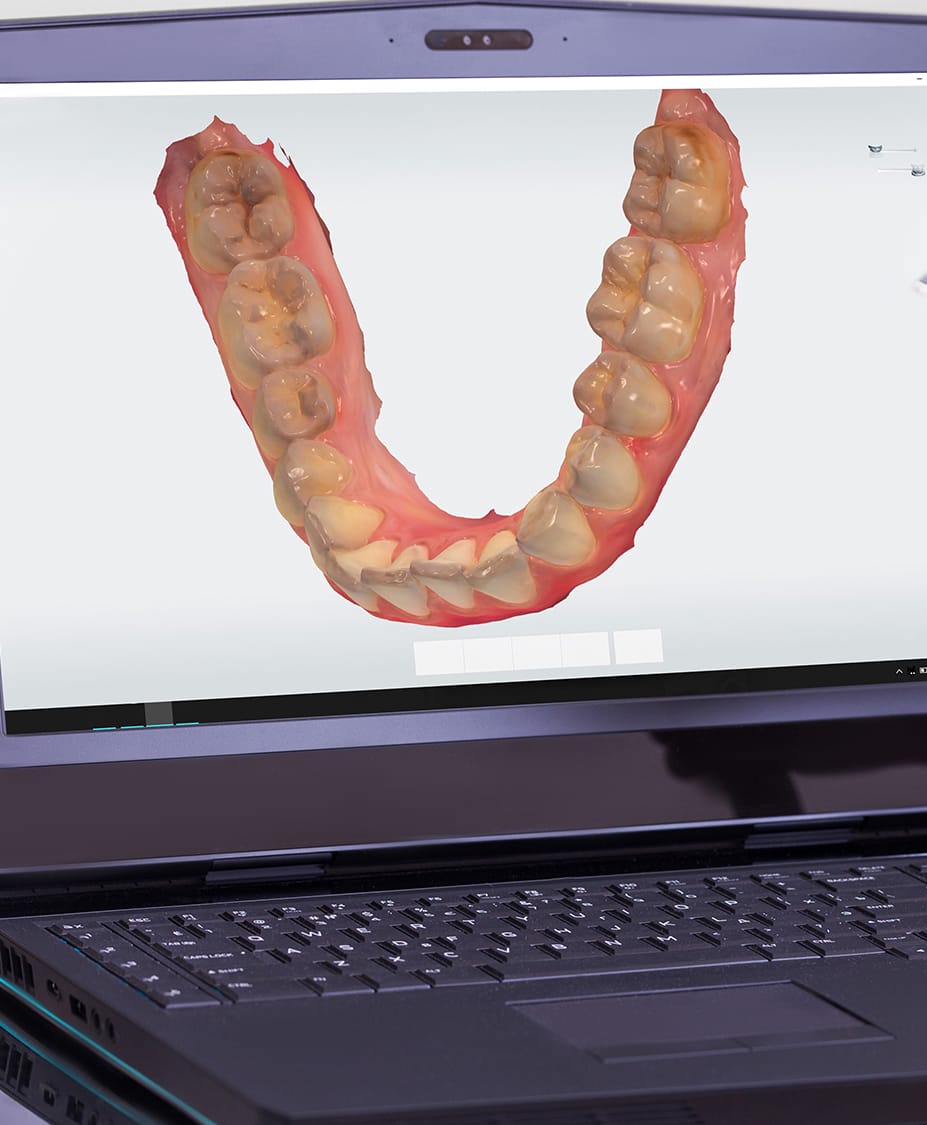

3shape Smile Design

Immerse yourself in the artistic beauty of 3shape Smile Design through substantial collections of inspiring images. blending traditional techniques with contemporary artistic interpretation. transforming ordinary subjects into extraordinary visual experiences. The 3shape Smile Design collection maintains consistent quality standards across all images. Ideal for artistic projects, creative designs, digital art, and innovative visual expressions All 3shape Smile Design images are available in high resolution with professional-grade quality, optimized for both digital and print applications, and include comprehensive metadata for easy organization and usage. Our 3shape Smile Design collection inspires creativity through unique compositions and artistic perspectives. Instant download capabilities enable immediate access to chosen 3shape Smile Design images. Our 3shape Smile Design database continuously expands with fresh, relevant content from skilled photographers. The 3shape Smile Design collection represents years of careful curation and professional standards. Diverse style options within the 3shape Smile Design collection suit various aesthetic preferences. Multiple resolution options ensure optimal performance across different platforms and applications. Professional licensing options accommodate both commercial and educational usage requirements. Each image in our 3shape Smile Design gallery undergoes rigorous quality assessment before inclusion. Time-saving browsing features help users locate ideal 3shape Smile Design images quickly. Advanced search capabilities make finding the perfect 3shape Smile Design image effortless and efficient.